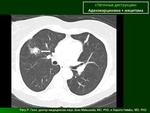

КТ ОГК, прошу помочь с интерпретацией изменений в легких.

Поступил тяжелый мужчина 1957 года рождения, кахексия, брадикардия. На Д-учёте не состоял, пьющий. Что думаете, уважаемые коллеги?

Больной сельский, со слов медработника ФАПа  жена больгоно умерла от ТБ, не состояла на учете, тоже была пьющая. Так может справа мелкая туберкуломка, давшая отсев. Поступил с подозрением на инсульт, если бы не неврологическая симптоматика, навряд ли сам пришел в больницу (с изменениями в легких).

Когда один нативе трудно что то разобрать)) особенно обычным рентгенологам. Да и без архива...Пока похоже на пневмонию и туберкулому.

Какие показатели плотности образования справа? Проводили ли контрастирование? Хотелось увидеть сканы в другом окне. Изменения интерстициальные, ДД пневмония, ТБЦ, наблюдение.

Без изображений во втором  окне (средостенном режиме) можно предполагать   многое. Справа в нижней доле (S10) пневмония. Наличие небольшого количества жидкости в плевральных полостях, больше справа. Признаки "застоя" в задне-базальных отделах обоих легких, на фоне которых предполагаются мелкие очаговые образования. В таких случаях проводиться методика сканирования ОГК на животе для исключения синдрома гравитации и признаков застоя, улучшается визуализация легочного рисунка, исключается или подтверждается наличие очаговых изменений, оценка наличия жидкости в плевральных полостях.  Ждем дальнейших изображений.

Контрастирование не проводили, больной был  невменяемый (не ориентировался в обстановке). Легкие сделали для исключения онко- кахексия.

По нативным изображениям. ГМ: постишемические изменения с кистообразованием

в передних отделах правой теменной области, гидроцефалия смешанного типа.

ОГК: туберкулема средней доли (S4) правого легкого, пневмония в нижней доле (S10) правого легкого,

незначительный гидроторакс справа, коронароатеросклероз, перикардит?

А, "туберкулёма" довольно хреновая, на рачок похожа.

В легких вероятно ТБЦ. Выраженный кальциноз коронарных артерий. Аневризма левого желудочка.

Согласен: "туберкулема" некрасивая. При адекватном состоянии пациента в таком случае была бы показана пункционная биопсия.

Спасибо за комментарии, но я за диссеминациюsad.   Хоть и мало видела на СКТ   тбсных  больных еще, больной тяжелый, как сказала невролог за выходные он  умрет. Но учитывая  внешний вид- кахексию, анамнез- пьет постоянно, что можно и нельзя, результаты анализов еще не знаю, туб контакт. Если даже и помрет, то дианоз не установим точный. Паталогоанатом на учебе (никто его вскрывать и не будет), а заключение нарисовать надо.

На представленных изображениях - картина внутрибронхиального распространения какой-то инфекции (центрилобулярные плотности). Это может быть туберкулез (за - наличие первичного узла), это  может быть бронхиолит с пневмонией (за - консолидация справа). Туберкулез можно исключить/подтвердить иммунодиагностикой (напр., Манту). Если пугает термин "бронхиолит" можно остановиться на "диффузной очаговой пневмонии" http://lekmed.ru/info/arhivy/differencialnyi-diagnoz-pnevmonii_9.html